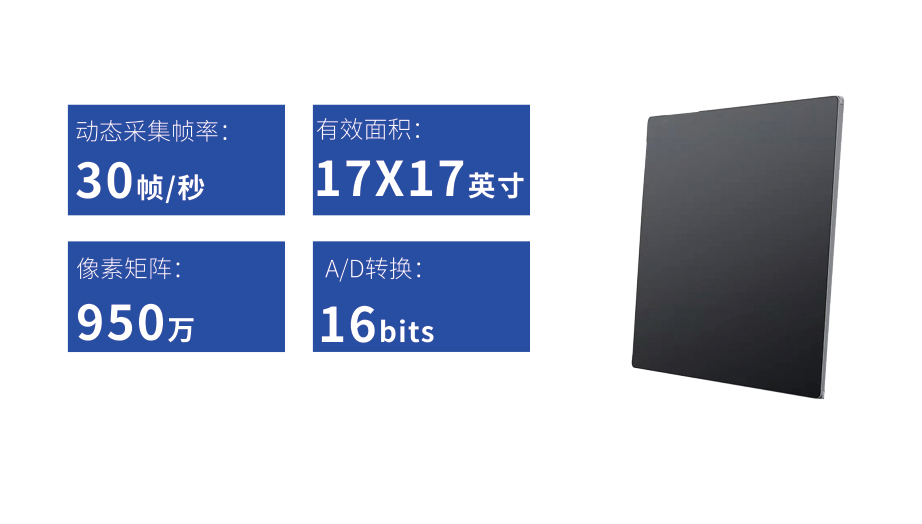

动态平板DRF

多功能、全视角、真视界,全面突破传统X线摄影透视理念,通过一块新型动态平板探测器,在检查中既可实现数字透视又可实现数字摄影,还可做数字胃肠及数字造影检查。

● 只需一块动态平板探测器,高效轻松实现摄影、透视和造影功能,几乎可以满足医院全科室